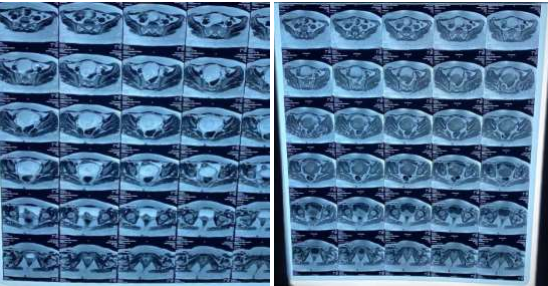

Pelvic ultrasound showed a left dermoid ovarian cyst. The abdominal MRI pelvis with contrast showed a mass lesion of about 12.5cm vertically, 11.5cm TS and 10cm in AP diameter in the cul de sac space, encapsulated in tough capsule and consist of fluid signals, soft tissue and fat signals with some tiny foci of very low signal intensity on all pulse sequences which may stand for calcification. All the serum tumor markers were normal.

Fig 1.2: Horizontal view

Fig 1: Preoperative abdominopelvic Magnetic resonance imaging with contrast demonstrating a mass lesion of about 12.5cm vertically ,11.5cm TS and 10cm in AP diameter in the cul de sac space, encapsulated in tough capsule; consist of fluid signals, soft tissue, fat signals and calcifications.